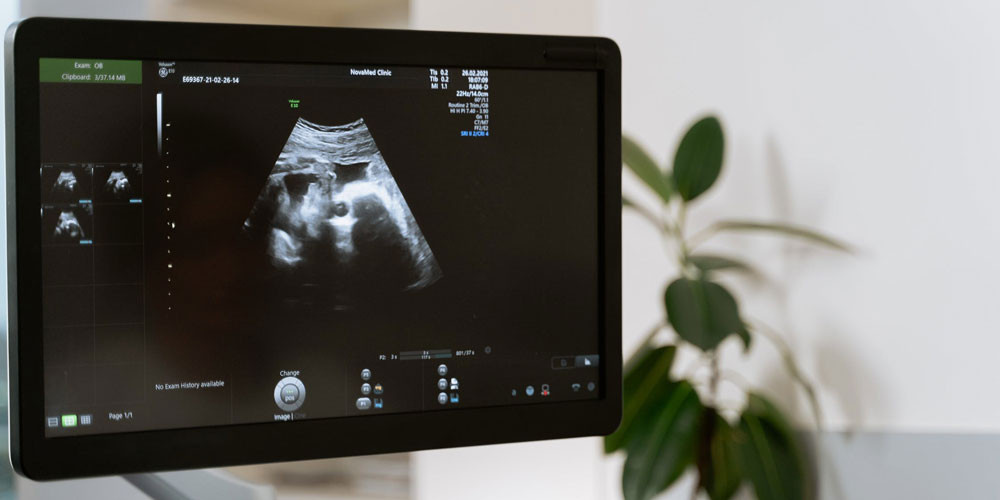

Раньше для определения проходимости маточных труб и изучения состояния яичников использовали сложные и болезненные методы. УЗИ-аппараты для акушерства помогают врачам быстро, с высокой точностью проводить исследования. Картинка, которую видит на мониторе специалист, четкая и информативная. Неудобства, испытываемые пациенткой, минимальны.

Сейчас во время ультразвукового исследования специалист видит анатомические особенности плода, состояние кровотока, движение пальцев. А при удачном расположении ребенка, достаточно рано можно определить даже его пол. В медицине появилось направление, изучающее состояние еще не родившего малыша — «медицина плода».

УЗИ-исследование — эффективный метод диагностики здоровья ребенка во время беременности.